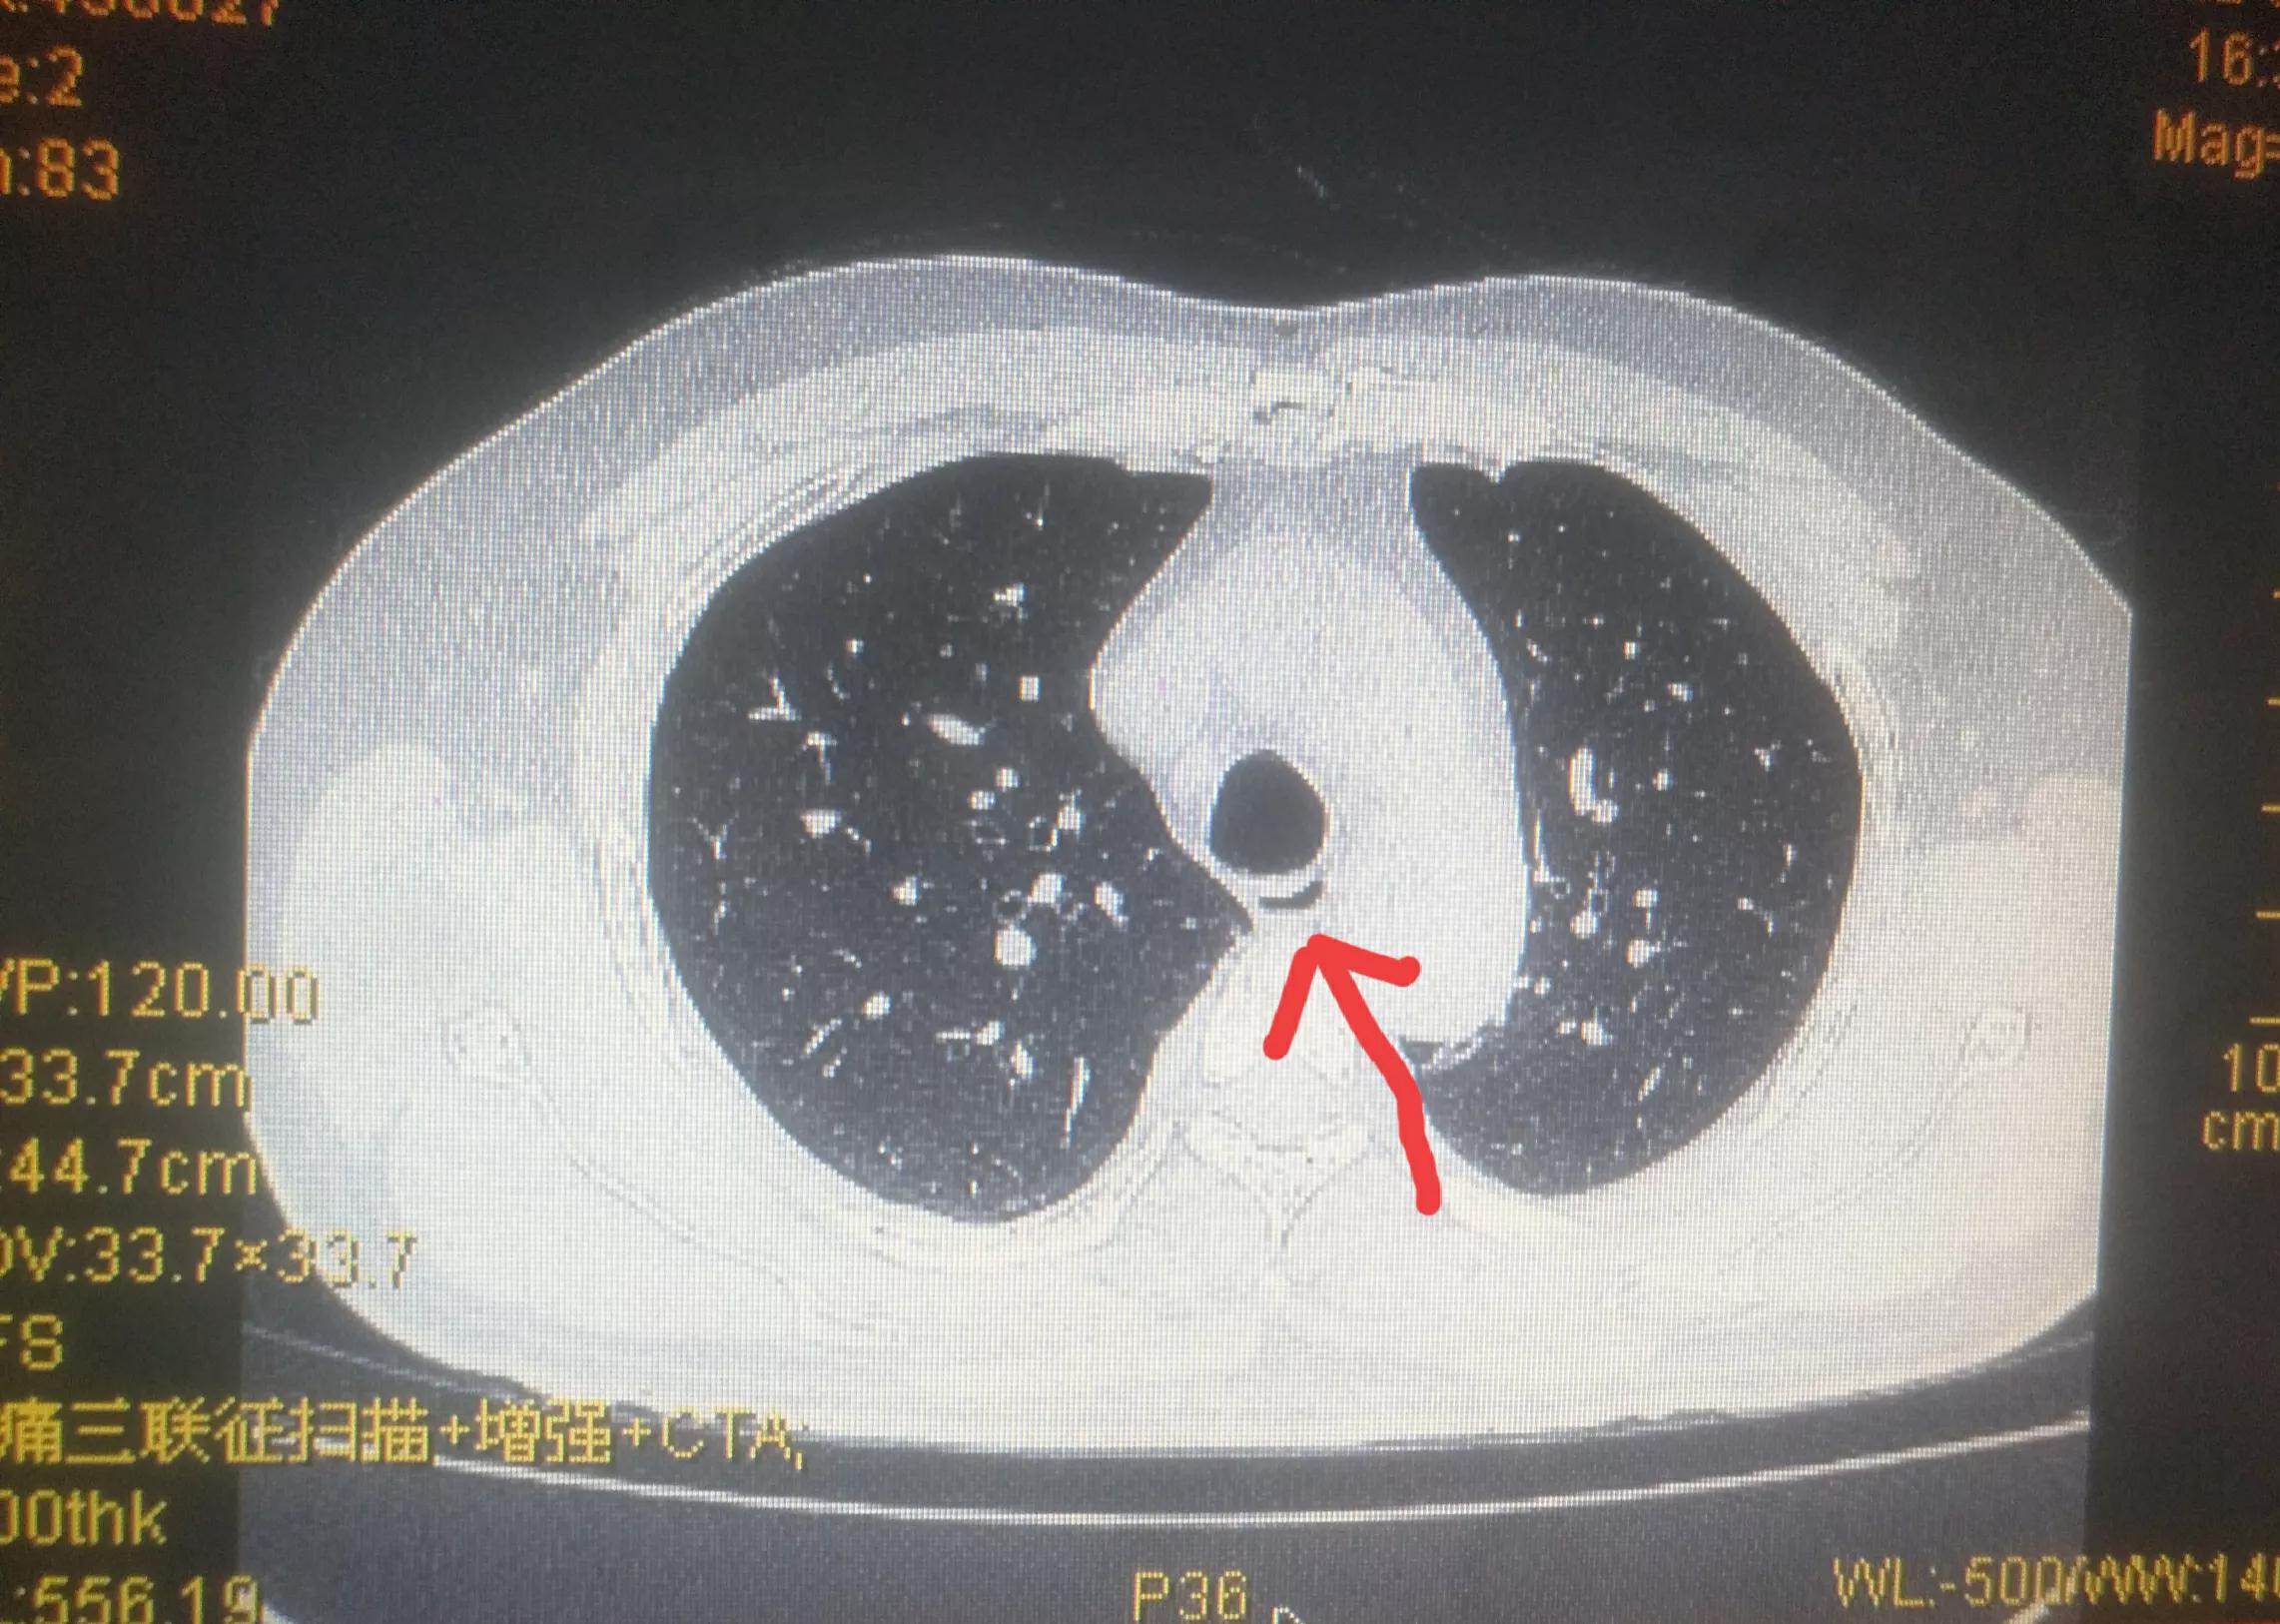

通过CT检查,黄先生确诊为主动脉夹层。

患者CT图:箭头处即为主动脉分离的内膜